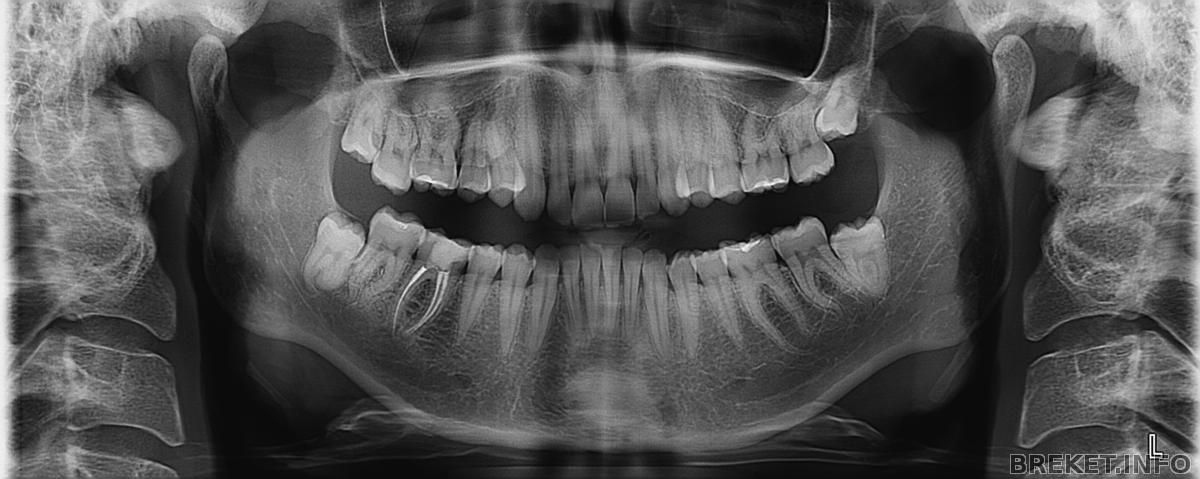

Основную подготовку к установке я прошла - сделала снимки и удалила восьмерки на ВЧ. Осталось только еще раз сходить к ортодонту, окончательно выбрать и заказать БС (предварительно это керамика спереди и металл на задних зубах) и назначить день установки.

И да, из фото пока могу предложить на ваше обозрение только снимки, но обещаю исправиться!)) ![]()